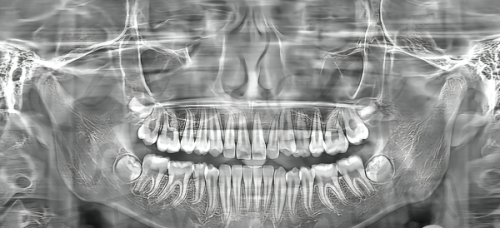

医院拥有一系列精良的诊疗设备,这些设备在口腔诊疗中发挥着重要作用。例如,口腔CT设备可以清晰地显示患者口腔内部的结构,包括牙齿、牙槽骨等情况,帮助医生正确诊断病情,制定更加科学合理的治疗方案。数字化口扫设备能够快速、正确地获取患者牙齿的三维模型,为正畸治疗提供严谨的数据支持,减少患者的就诊时间和不适感。